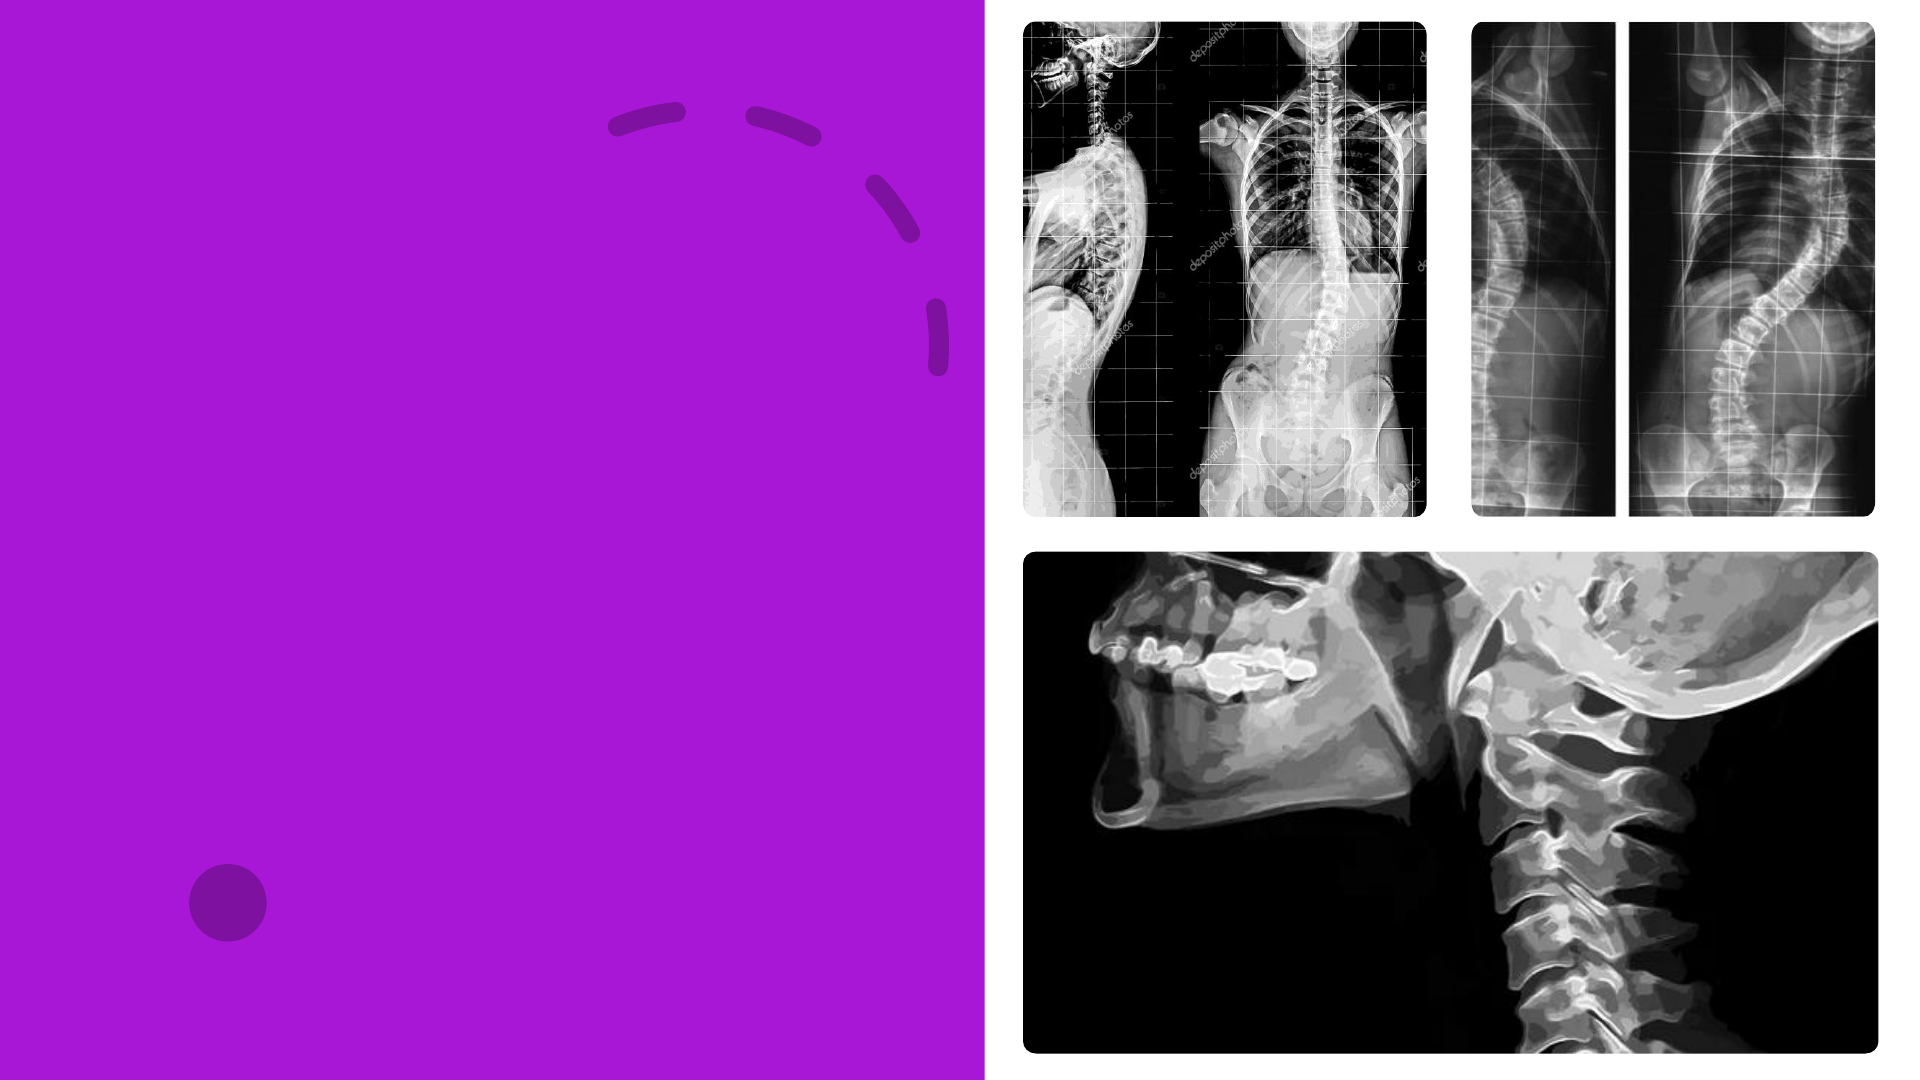

<p>Cinesiologia</p><p>do pescoço e</p><p>tronco</p><p>Prof. Ms. Yuri Montenegro</p><p>Revisão</p><p>• Planos e eixos de movimentos</p><p>• Tipos de articulações.</p><p>• Estruturas ósseas que compõem a coluna vertebral.</p><p>Crânio:</p><p>estruturas ósseas</p><p>(LIPPERT, 2018)</p><p>Crânio:</p><p>estruturas ósseas</p><p>(LIPPERT, 2018)</p><p>Crânio:</p><p>Articulação temporomandibular</p><p>(LIPPERT, 2018)</p><p>Articulação temporomandibular:</p><p>movimentos</p><p>(LIPPERT, 2018)</p><p>Músculo temporal</p><p>(LIPPERT, 2018)</p><p>Músculo masseter</p><p>(LIPPERT, 2018)</p><p>Músculo pterigóideo</p><p>(LIPPERT, 2018)</p><p>Músculo pterigóideo</p><p>(LIPPERT, 2018)</p><p>Coluna:</p><p>estruturas ósseas</p><p>(LIPPERT, 2018; THOMPSON, 2011)</p><p>Coluna:</p><p>estruturas ósseas</p><p>(HAMILL; KNUTZEN; DERRICK, 2016)</p><p>Coluna cervical:</p><p>articulações</p><p>(HAMILL; KNUTZEN; DERRICK, 2016)</p><p>+/- 10º~15º de flexão e extensão</p><p>Articulação atlantoccipital</p><p>+/- 10º de flexão e extensão</p><p>+/- 47º~50º de rotação.</p><p>Articulação atlantoaxial</p><p>Coluna vertebral:</p><p>articulações</p><p>(HAMILL; KNUTZEN; DERRICK, 2016)</p><p>Coluna vertebral:</p><p>articulações</p><p>(HAMILL; KNUTZEN; DERRICK, 2016)</p><p>Coluna vertebral:</p><p>articulações</p><p>(HAMILL; KNUTZEN; DERRICK, 2016)</p><p>Coluna vertebral:</p><p>movimentos</p><p>(HAMILL; KNUTZEN; DERRICK, 2016;LIPPERT, 2018)</p><p>Coluna vertebral:</p><p>Movimentos.</p><p>(HAMILL; KNUTZEN; DERRICK, 2016)</p><p>Coluna vertebral:</p><p>Movimentos.</p><p>(HAMILL; KNUTZEN; DERRICK, 2016)</p><p>Ritmo lombopélvico</p><p>(HAMILL; KNUTZEN; DERRICK, 2016)</p><p>Músculos do pescoço</p><p>(LIPPERT, 2018)</p><p>Músculos do pescoço</p><p>(LIPPERT, 2018)</p><p>Músculos do tronco</p><p>(LIPPERT, 2018)</p><p>Músculos do tronco</p><p>(LIPPERT, 2018, 2019)</p><p>Músculos do tronco</p><p>(LIPPERT, 2018, 2019)</p><p>(HAMILL; KNUTZEN; DERRICK, 2016)</p><p>(HAMILL; KNUTZEN; DERRICK, 2016)</p><p>(HAMILL; KNUTZEN; DERRICK, 2016)</p><p>(HAMILL; KNUTZEN; DERRICK, 2016)</p><p>(HAMILL; KNUTZEN; DERRICK, 2016)</p><p>Bibliografia</p><p>HAMILL, J.; KNUTZEN, K. M.; DERRICK, T. R. Bases biomecânicas do</p><p>movimento humano. 4. ed. Barueri: Manole, 2016.</p><p>LIPPERT, L. Cinesiologia clínica e anatamoia. 6. ed. Rio de Janeiro:</p><p>Guanabara Koogan, 2018.</p><p>OATIS, C. A. Cinesiologia: a mecânica e a patomecânica do movimento</p><p>humano. 2. ed. Barueri: Manole, 2014.</p><p>SPINDLER, V.; WASCHKE, J. Membro superior. In: WASHCKE, J. Sobotta</p><p>anatomia clínica. Rio de Janeiro: Elsevier, 2019.</p><p>Cinesiologia</p><p>da cintura</p><p>pélvica</p><p>Prof. Ms. Yuri Montenegro</p><p>Slide 1: Cinesiologia do pescoço e tronco</p><p>Slide 2: Revisão</p><p>Slide 3</p><p>Slide 4</p><p>Slide 5</p><p>Slide 6</p><p>Slide 7</p><p>Slide 8</p><p>Slide 9</p><p>Slide 10</p><p>Slide 11</p><p>Slide 12</p><p>Slide 13</p><p>Slide 14</p><p>Slide 15</p><p>Slide 16</p><p>Slide 17</p><p>Slide 18</p><p>Slide 19</p><p>Slide 20</p><p>Slide 21</p><p>Slide 22</p><p>Slide 23</p><p>Slide 24</p><p>Slide 25</p><p>Slide 26</p><p>Slide 27</p><p>Slide 28</p><p>Slide 29</p><p>Slide 30</p><p>Slide 31: Bibliografia</p><p>Slide 32: Cinesiologia da cintura pélvica</p>